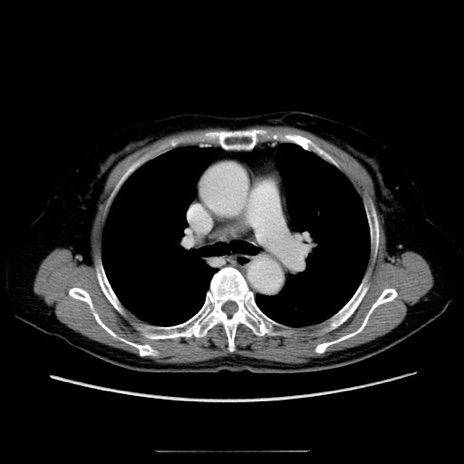

冠状断像

【症例】70歳代女性

【主訴】お腹が張る

【現病歴】1週間くらい前から腹部膨満の自覚あり。昨日夜から増悪したため、本日救急外来受診。

【身体所見】意識清明、BT 36.5℃、BP 165/106mmHg、HR 80bpm、SpO2 98%、腹部:膨満、軟、自発痛・圧痛なし、触診にて不快感あり、腸蠕動音:減弱

【データ】WBC 12600、CRP 1.04